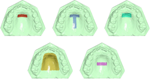

Three-Dimensional Analysis of Posterior Mandibular Displacement in Rats. Lyros I, Ferdianakis E, Halazonetis D, Lykogeorgos T, Alexiou A, Alexiou K-E, Georgaki M, Vardas E, Yfanti Z, Tsolakis AI. Vet Sci 2022;9,144. doi: 10.3390/vetsci9030144. PMID: 35324872.